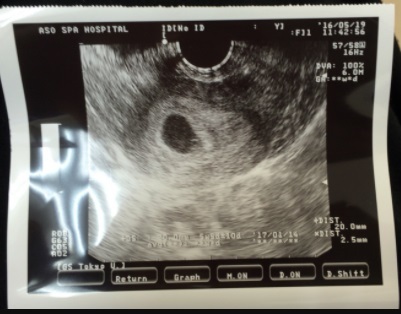

6週1日(6w1d・女の子)|shiori_sna さん(23歳)

エコー写真撮影時のエピソード:

このエコー写真は初めて病院に行ってエコーしてもらったときのです。 形はまだ見えないけどお腹に赤ちゃんがいるって実感した1枚です。

まだ6週でこれからちゃんと育ってくれるか不安だったけど無事生まれて来てくれたのでうれしかったです。